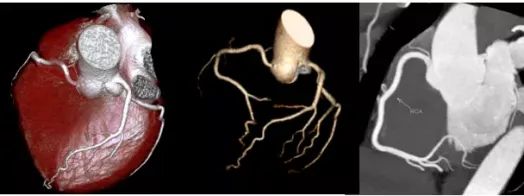

为满足广大市民日益增长的医疗服务需求,阆中市人民医院坚持以百姓健康需求为导向,引进川东北首台西门子SOMATOM Drive256层量子双源CT,已于近日在医院放射科正式启用。它采用全球独创的双球管结构,具有扫描速度快,图像质量高,辐射剂量低等特点,临床应用领域广泛,在全身各部位的无创成像方面开创了高端CT应用的新纪元。此设备的投入使用,为需要做增强CT的肾衰竭患者及心脑血管联合扫描、早期肿瘤检测等患者带来福音,尤其在心脏冠脉成像方面具有无可比拟的优势,其操作便捷、安全无创和绿色环保引领着业内的标杆和典范,被称为窥心神器。标志着阆中市人民医院影像诊断技术步入了超精细化时代,对提升医学影像诊断水平具有重要意义。

SOMATOM Drive 量子双源CT是西门子全新的双源平台,它搭载了全新IGBT技术的Sigma球管、Stellar光子探测器和三域迭代重建等一系列革新技术,开辟了CT智慧影像链新时代。Drive CT具有快速、精准、安全的临床特点,对心脏冠脉检查、肿瘤筛查及随访、超低剂量体检、低对比剂应用和大范围血管检查等方面具有显著的优势。

Drive双源CT的单扇区时间分辨率达到75ms,在最为复杂的心脏成像中对图像的“冻结”能力更强,真正实现了“无限制”心脏冠脉CT检查,两次吸气憋气就可以完成检查过程,图像也更加清晰。一次10秒左右的扫描即可获得整个躯干包括肺、心脏、血管及其他脏器在内的全部组织结构信息。

SOMATOM Drive CT可以实现一张胸片的辐射剂量下获得全肺的筛查CT图像,三张胸片的辐射剂量下完成冠脉CTA扫描。X线剂量较以往设备下降60%~80%,在获取高质量影像图片的同时,也保证了低剂量带来的CT检查安全。SOMATOM Drive CT行血管CTA检查(如冠状动脉、头颈部血管、全主动脉、下肢动脉CTA等检查),对比剂使用量仅为之前CTA检查的一半。

三、图像更清晰

搭载的Stellar Infinity光子探测器,能够清晰成像。搭配全新算法,软硬件结合使图像质量得到进一步提升。并且利用双能量扫描技术,去除体内金属植入物(脊柱金属固定器、动脉瘤夹闭器等)所造成的伪影,有助于更好地观察及评估术后固定器及周围软组织。